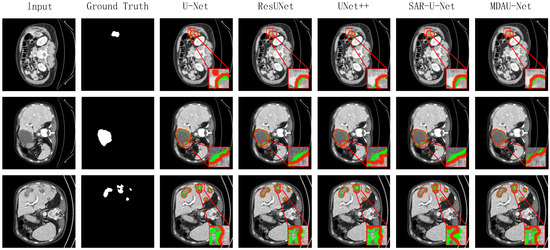

5.1. Quantitative Analysis of Liver Segmentation

5.2. Quantitative Analysis of Liver Tumor Segmentation